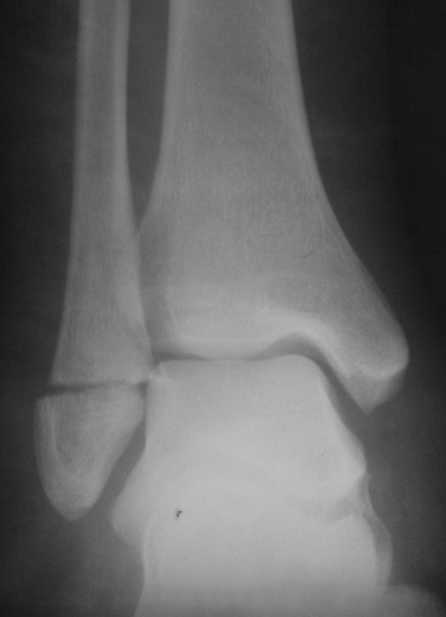

На одном из форумов заспорили о тактике.Женщина 23 года, рост 158, вес 55, профессия: менеджер, хобби: верховая езда, горные лыжи, велосипеды, не курит, сопутствующих заболеваний нет.28 июня упала с лошади.первый рентген:

Вечер добрый! Судя по представленным рентгенограммам (с интервалом почти в два месяца!?) перелом не сросся. Лично я склоняюсь больше в сторону оперативного лечения (с учетом анамнеза пациентки). Но для принятия окончательного решения хотелось бы, для начала, увидеть снимки обоих суставов в сравнении в двух проекциях , а также сравнительные - фас под нагрузкой. При отсутствии жалоб со стороны пациентки на сегодняшний день (при данной рентгенологической картине), они (жалобы) ,скорее всего, появятся позже.

Ничего удивительного в том, что мнения хирургов разошлись нет, поскольку в целом в мире разные хирурги исповедуют разные тактики лечения переломов наружной лодыжки. Так одни считают, что нужно оперировать даже при смещении в 1 мм, другие допускают 5 мм. В среднем считают «цифрой старта» 2-3 мм. Но все сходятся в том, что нужно ориентироваться на функциональные запросы пациента. Но в вашем случае уже не свежий перелом, а замедленная консолидация со смещением отломков. (Delayed malunion? :-{)

Андрей, я всё таки склонен считать, что принципиального разногласия нет. На сегодняшний день рекомендовать оперативное лечение меня заставили следующие факторы:

1. Увеличивающийся диастаз фрагментов,

2. Отсутствие на рентгеновских снимках признаков образования костной мозоли, с одной стороны и

3. Образование кортикальной замыкательной пластинки на проксимальном фрагменте в зоне контакта, с другой,

1- Диастаз увеличивается. За счет чего? Сам дистальный отломок наружной лодыжки как был на месте, так и стоял. Т.е. увеличение диастаза не за счет подвижности и нестабильности, а за счет резорбции.

Данный перелом по классификации Вебера относится к типу А- т.е. дистальнее синдесмоза. В этом месте малоберцовая кость не несёт никакой нагрузки. Прошло только 2 месяца с момента перелома дайте больной что-то типа Air cast на месяц-полтора и полную нагрузку на ногу и сгибательно-разгибательные движения в суставе.